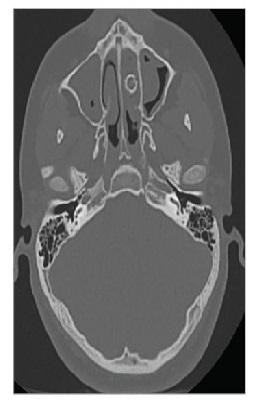

Viên đạn trong mũi 8 năm mà không biết

Một thiếu niên 15 tuổi, ở Mỹ vô tình bị viên đạn lọt vào mũi suốt 8 năm, gây ra "mùi hôi" kinh khủng khi xì mũi. Gia đình cậu bé tiết lộ rằng, cậu đã bị bắn vào mũi bằng súng bắn đạn bi lúc khoảng 8 hoặc 9 tuổi. Dần dà, viên đạn đã chặn các đường dẫn lưu trong mũi của cậu bé, dẫn đến sự tích tụ của chất nhầy, các mảnh vụn và vi khuẩn gây ra mùi hôi. Sau cuộc phẫu thuật của cậu bé, mùi hôi khó chịu đã biến mất.